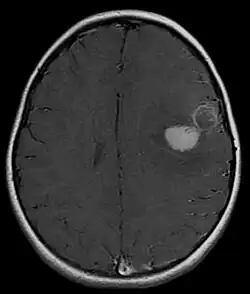

Supratentorial central PNET in a 5-year-old patient

PNET of the CNS generally refer to supratentorial PNETs.